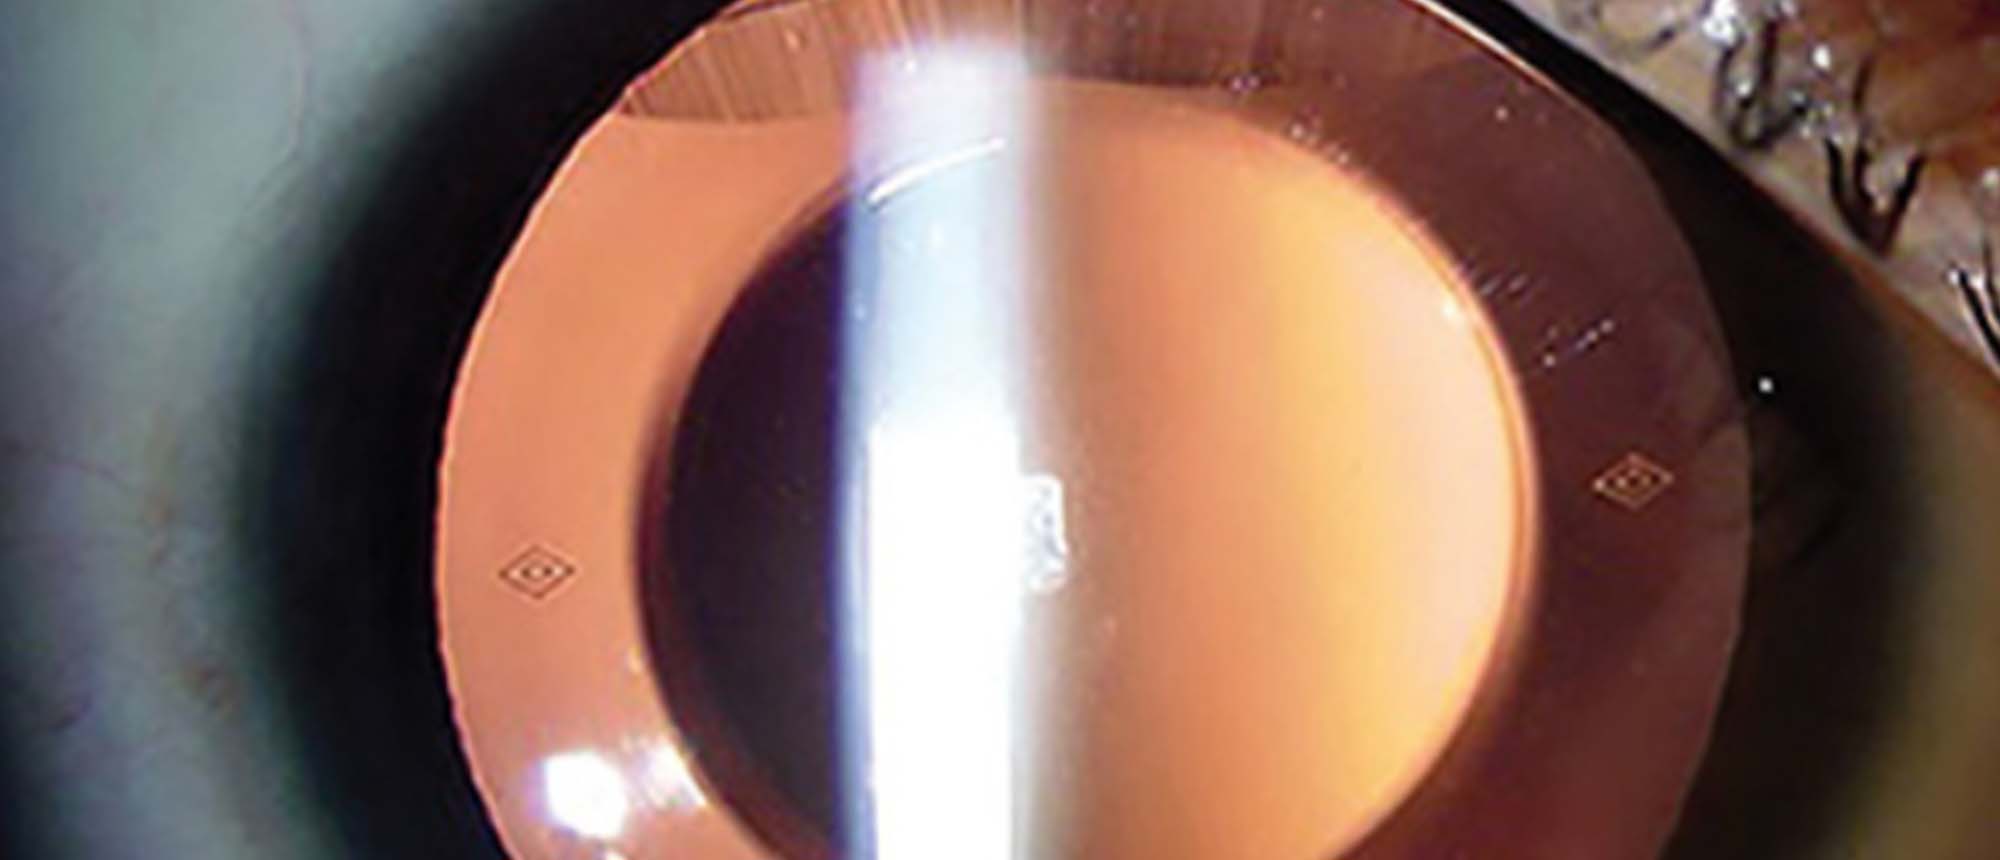

Pseudophakic Bullous Keratopathy with Prior Descemet Membrane Tears due to Forceps Trauma

Presenter(s): Christopher Seery, MD

Faculty Discussant(s): Ellen Koo, MD

Abstract A patient with a history of forceps trauma at birth and amblyopia of the left eye who presents with persistent corneal edema 1 year after uncomplicated cataract surgery. Initial visual acuity was 20/200, intraocular pressure was 10, and pachymetry was 698 um. On clinical examination there …